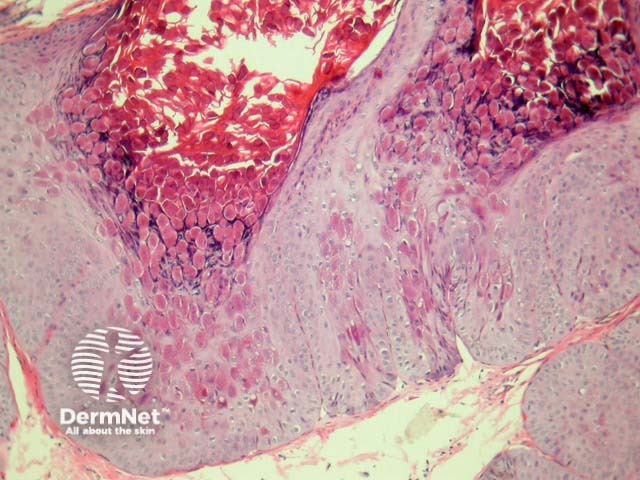

In molluscum contagiosum, there is usually pronounced infundibular hyperplasia and papillomatosis with central umbilication. (figure 1).

Millions of virions that have proliferated in the cytoplasm of affected epithelial cells result in the characteristic intracytoplasmic bodies that compress the keratinocyte nucleus (figure 2). This viral inclusion is the largest in all of human histopathology (figure 3).

Figure 1